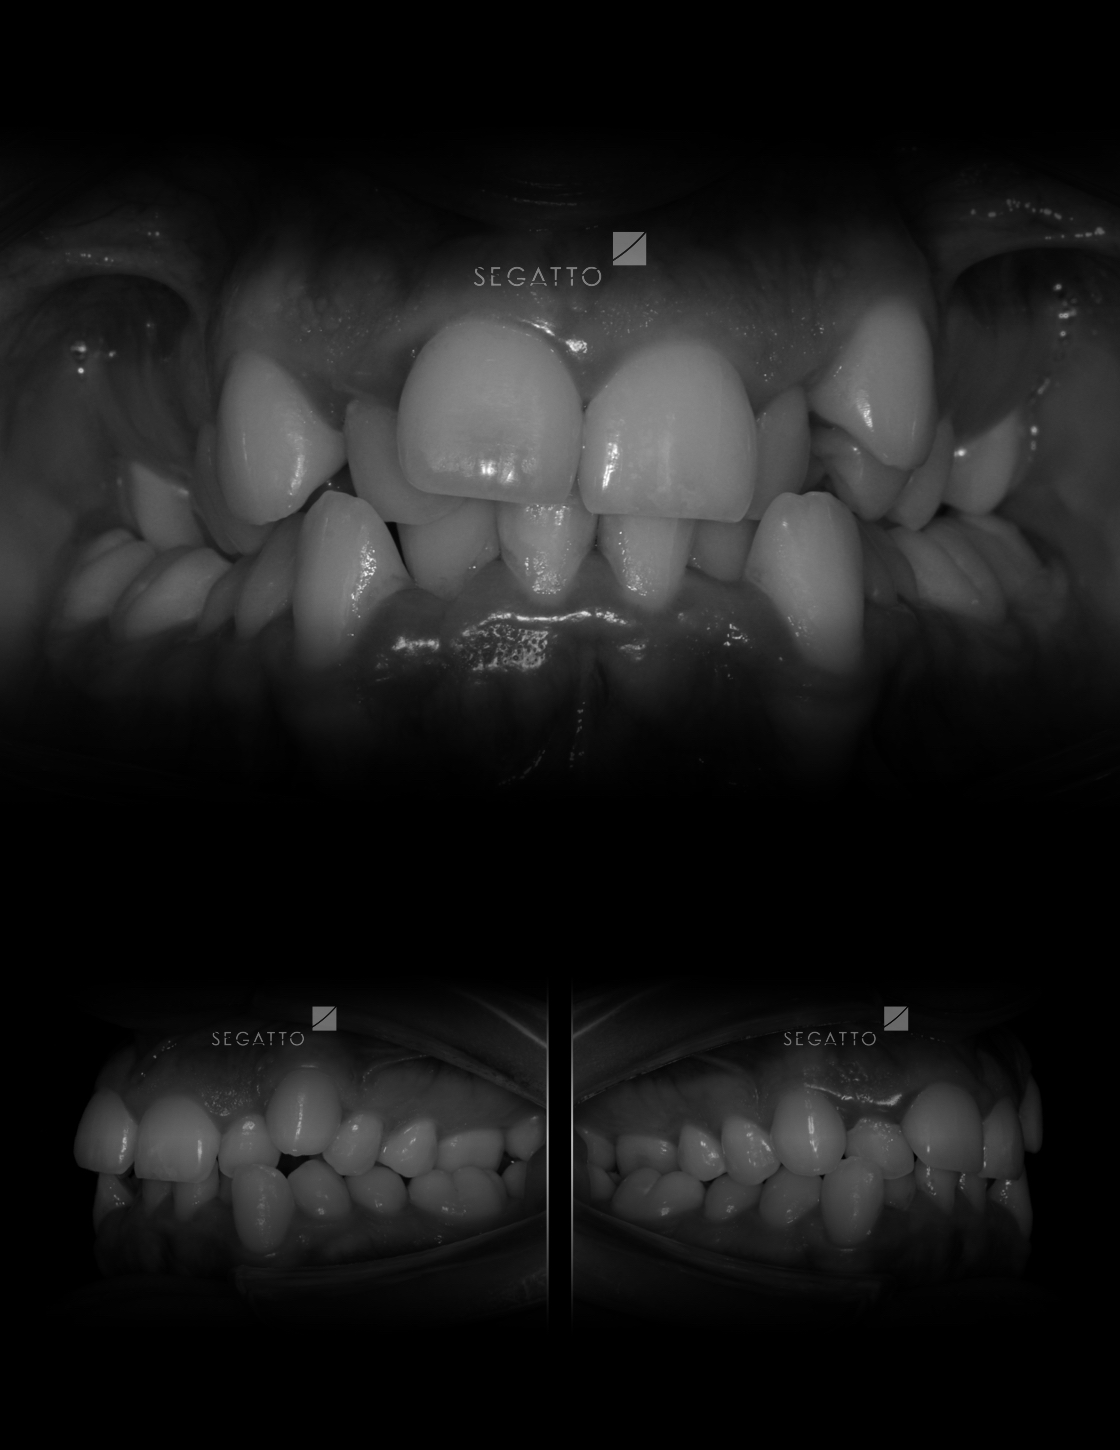

Orthodontics

Cases